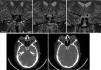

We present the case of a 45-year-old male diagnosed with acromegaly. Magnetic resonance imaging identified a marked dilatation and medialization of both cavernous internal carotid arteries (ICA), leading to a narrow intercarotid distance, a phenomenon known as “carotid kisses”.

This vascular alteration has been described in greater proportion in patients with acromegaly. The anomalies that are also present with greater prevalence in these patients are: aneurysms of the ICA, protrusion of the ICA into the sphenoid sinus, narrow intercarotid distance, fusiform dilatation of the ICA and dehiscence of this artery in the bony canal. The presence of such alterations increases the risk of injury to the ICA.